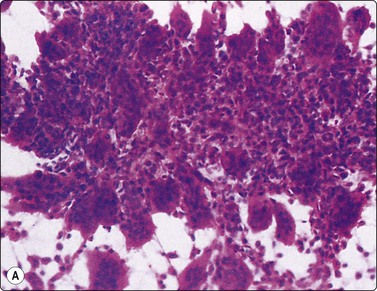

Langerhans cell histiocytosis presents as lytic and often well-defined lesions. Most cases are seen in children. The lesions may be solitary (most cases) or multiple. The long bones (femur and humerus) and the skull are the most common sites in children, and the pelvic bones and ribs in adults. The cytological pattern of Langerhans cell histiocytosis is fairly characteristic and may be diagnostic. The typical histiocytes have moderately larger and paler nuclei than those seen in common inflammatory processes. Generally reniform, the nuclei have a distinct irregular and folded outline (Fig. 16.10A). Coffee-bean nuclei has been reported to be typical of this lesion (Fig. 16.10B). The chromatin is entirely bland and nucleoli small. The cytoplasm is abundant and pale and has fairly well-defined borders. It is often vacuolated. In exceptional cases the Langerhans cells may show signs of phagocytosis. Multinucleated cells of similar type are commonly present. These can be quite large and may resemble osteoclasts in wet-fixed smears.

image image

Fig. 16.10 Langerhans cell histiocytosis (eosinophilic granuloma)

(A) Lytic bone lesion, many histiocytes with irregular reniform pale nuclei, some eosinophils (H&E, IP); (B) Coffee-bean nuclei have been reported to be typical of this lesion (H&E, HP, Oil)